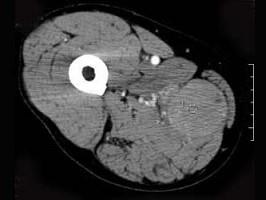

问题 男,30岁,主诉右大腿肿块年余,逐渐增大,局部胀痛及压痛,请根据图像表现,选出最佳选项 ( )

选项 A、横纹肌肉瘤 B、神经纤维瘤 C、血管瘤 D、脂肪瘤 E、脓肿

答案 A